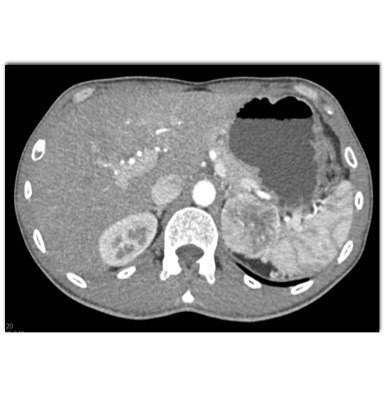

The most likely diagnosis in this case is?

adrenal lymphoma

pheochromocytoma

primary adrenal carcinoma

metastatic renal cell carcinoma